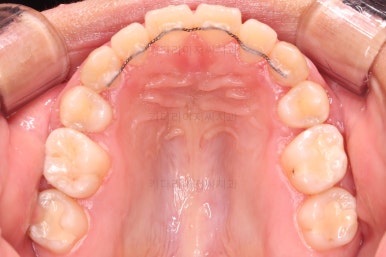

초진 때의 입안 모습입니다.

원래 다니던 치과에서 1년여 교정치료를 진행하신 상태였는데요.

몇 가지 이상한 점이 보이죠?

한 쪽만 발치가 되어있다.

아랫니에 유치가 2개가 그대로 남아있다.(화살표)

몇몇 이아에는 장치가 부착되어 있지 않다.

우선 X-ray를 확인해 봤을 때, 아랫니 유치는 상태가 나쁘지 않아 그냥 쓰려면 한동안 계속 쓸 수는 있겠으나 영구치만큼 오래 쓸 수 있다는 보장이 없었고요.

해당 위치의 원래 영구치보다 크기가 커서 교합을 맞추는데 있어서도 문제가 있었어요.

딱 한 개의 치아만 발치되어 있었는데 추가적으로 균형을 맞추기 위해 반대편 치아도 발치를 하고 아랫니 유치도 뽑았어요.

유치 어금니는 크기가 매우 크기 때문에 빈자리 만큼 모두 앞니를 뒤로 당기면 입이 너무 들어가게 된답니다.